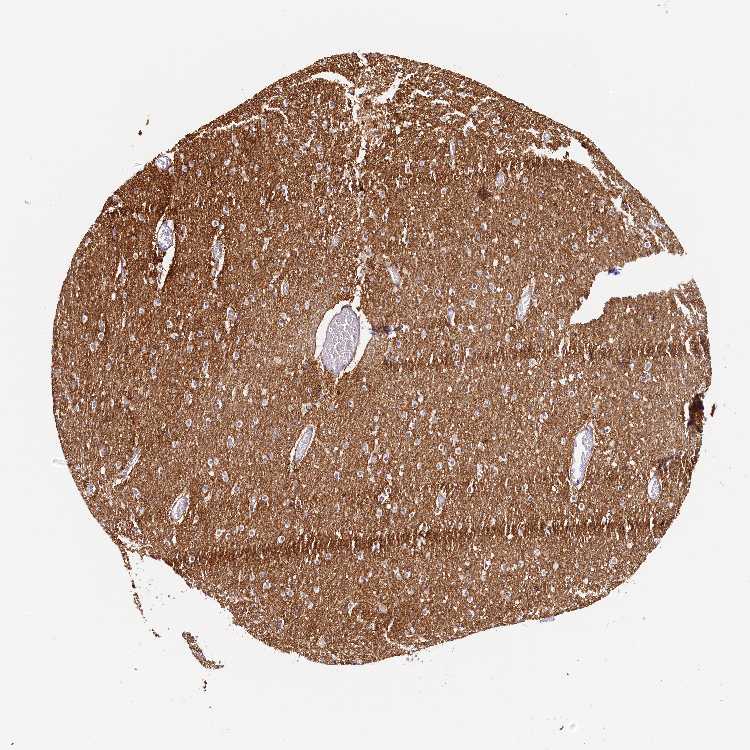

CEREBELLUM - Antibody stainingi

Antibody staining in the annotated cell types in the current human tissue is reported as not detected, low, medium, or high, based on conventional immunohistochemistry profiling in selected tissues. This score is based on the combination of the staining intensity and fraction of stained cells.

Each image is clickable and will lead to virtual microscopy that enables deeper exploration of all samples and also displays staining intensity scores, fraction scores and subcellular localization as well as patient and tissue information for each sample.

Antibody HPA040981

Purkinje cells Not detected

Cells in granular layer Medium

Cells in molecular layer Not detected